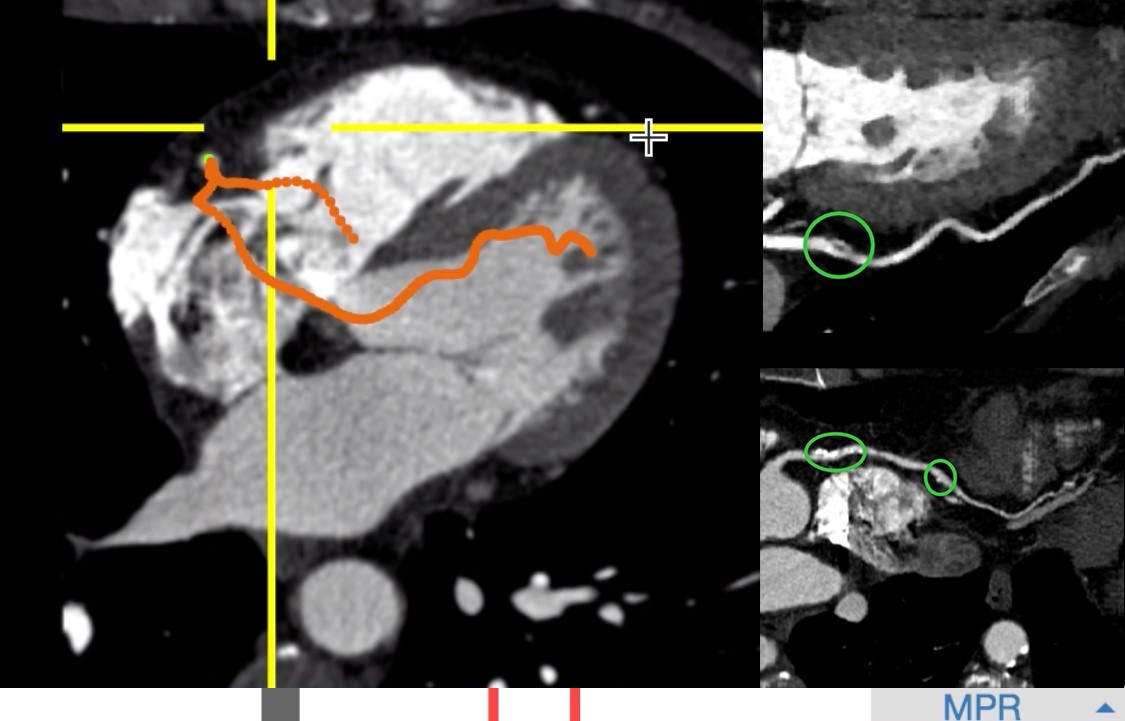

在临床上,心梗患者往往起病急,短时间内若不及时治疗便有生命危险。一般急诊心梗患者送至医院CT核磁科进行检查时,医生需放下手中所有工作、并高度集中注意力,细心准确地进行血管3D重建,并快速写出诊断报告,时间紧任务重,这对医生来说,压力非常大,一旦出错就容易错过宝贵的抢救时间。为此,阿里冠脉AI能在0.5秒内全自动提取的单根心脏冠脉,医生可从重建的影像上快速发现病灶(如图)。

阿里AI在0.5秒内全自动提取的单根心脏冠脉,医生可从重建的影像上快速发现病灶。右上为血管上的软斑块,右下为钙化斑块。